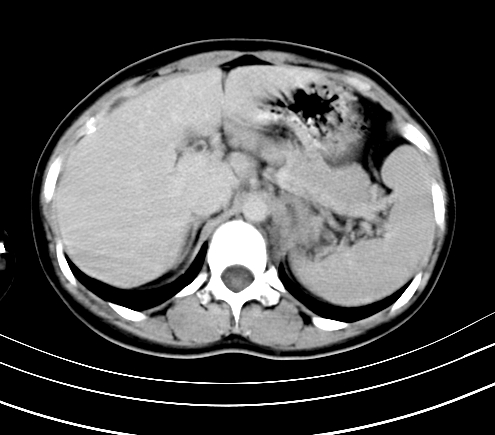

腹部平扫